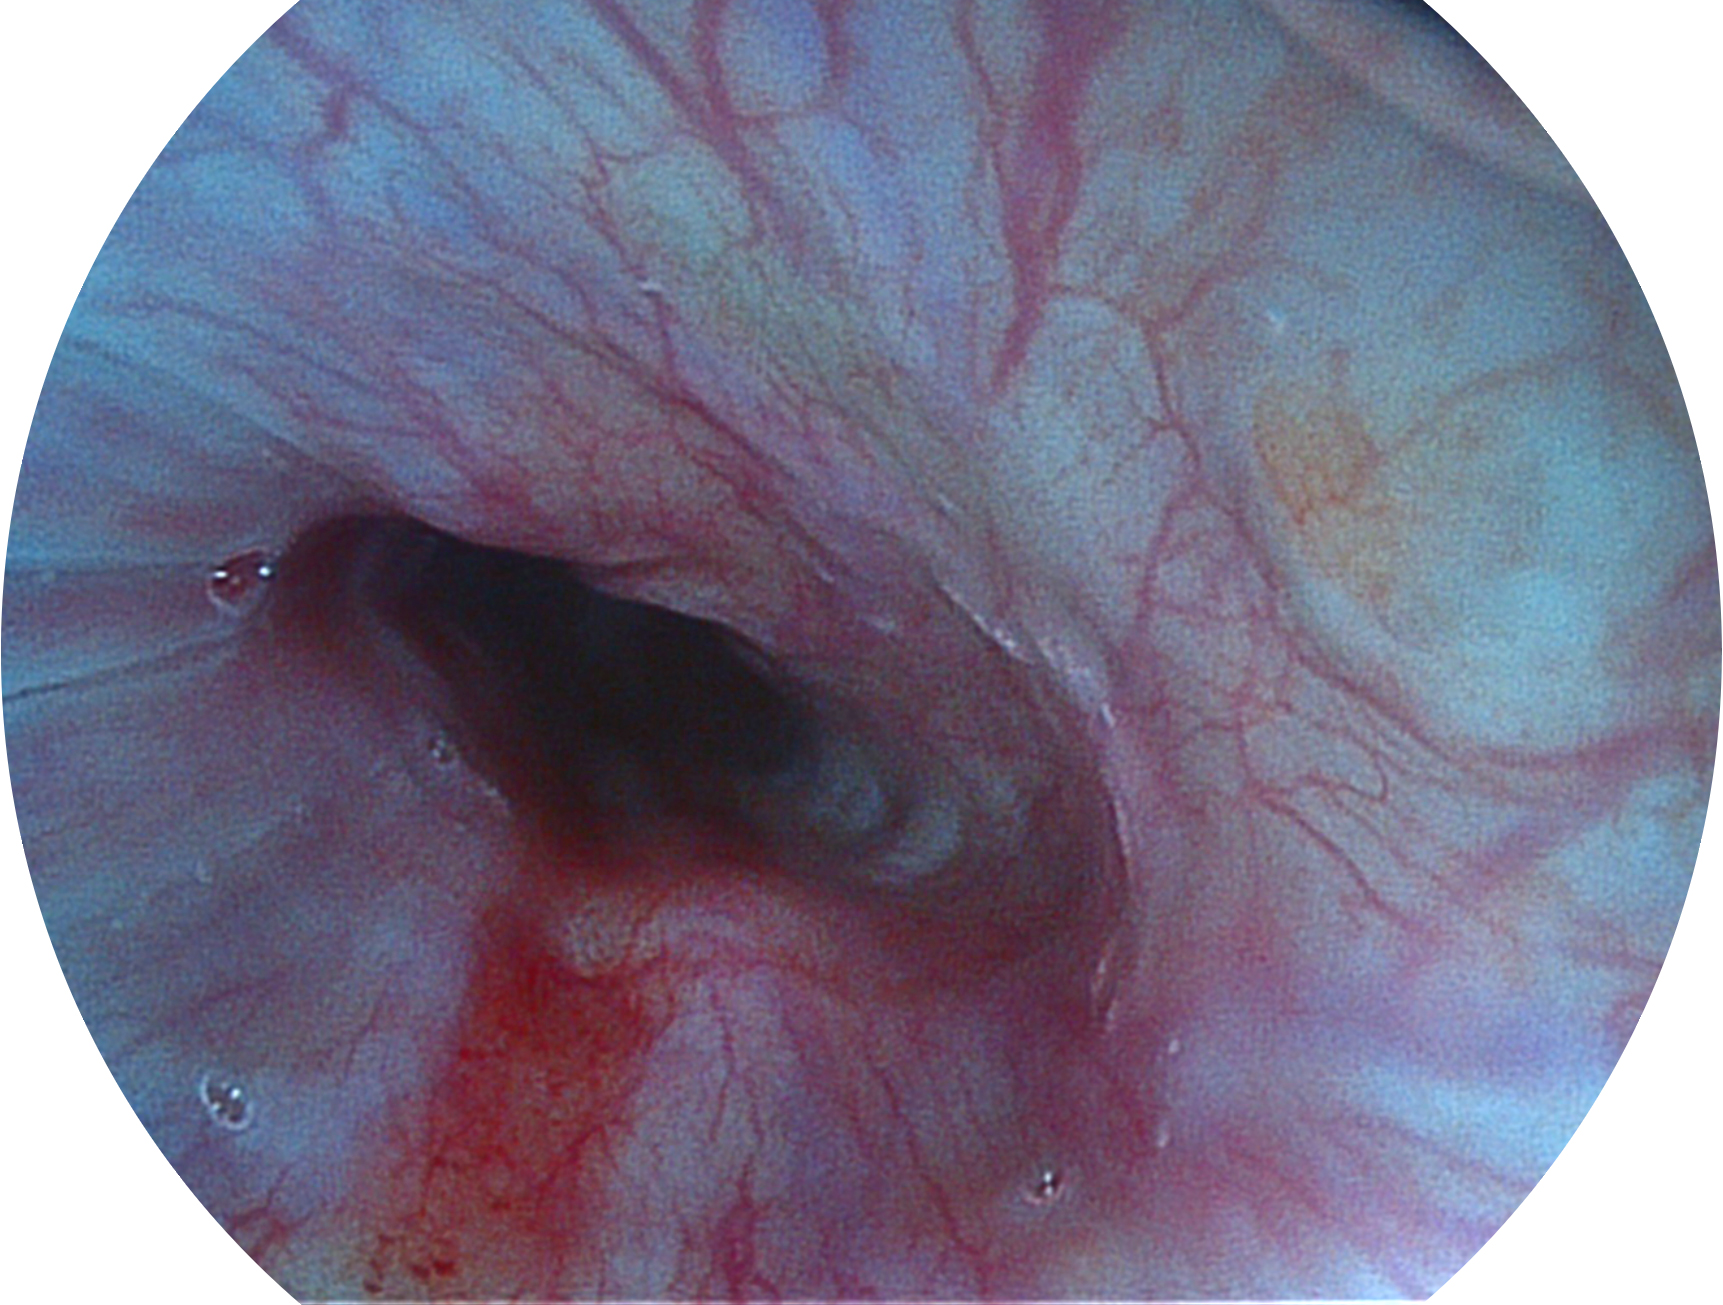

米兰官方网站新开发的内镜染色技术,主要是基于多波长LED 光源的开发,VLS-55Q 四波长LED 光源是由四个不同颜色的LED光按照相应照明模式所规定的特定发光比例进行合束后形成,合束后形成的照明光的光谱由红光、绿光、蓝光及蓝紫光这四个不同的波段范围构成。具有更高光谱自由度,通过光谱比例的控制,实现了聚谱成像技术,英文全称为“Spectral Focused Imaging, SFI”,缩写为“SFI”和光电复合染色成像技术,英文全称为“Versatile Intelligent Staining Technology, VIST”,缩写为“VIST”。